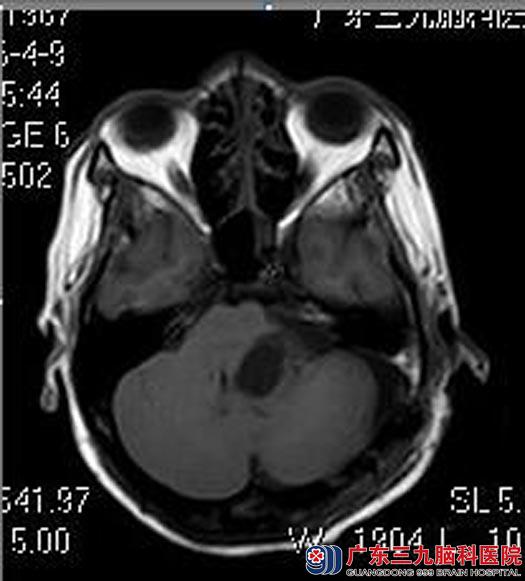

钟小姐一年前出现左侧耳鸣伴听力下降,在当地医院多次就诊未发现异常。二个月前出现左侧面部麻木不适,头晕伴有行走不稳,行头颅MRI检查发现“左侧桥小脑角占位性病变,考虑听神经瘤;梗阻性脑积水”。

住院在广东三九脑科医院综合神经外科,查体:左侧鼻唇沟变浅,左侧轻度面瘫,左侧面部有麻木感,闭目难立征(+)。

鲁明主任主刀,在全麻下行左侧听神经瘤切除术,术中见肿瘤位于左侧桥小脑角,黄白色,质中,显微镜下电凝分块切除,左侧听神经、面神经位于肿瘤前下方,分离面神经保留完整,三叉神经、舌咽神经受肿瘤压迫明显,细心分离完整保留,肿瘤全切。术后钟小姐自诉面部麻木感及耳鸣消失,听力较前好转,无明显后组颅神经损害症状。术后病理提示:神经鞘膜瘤。